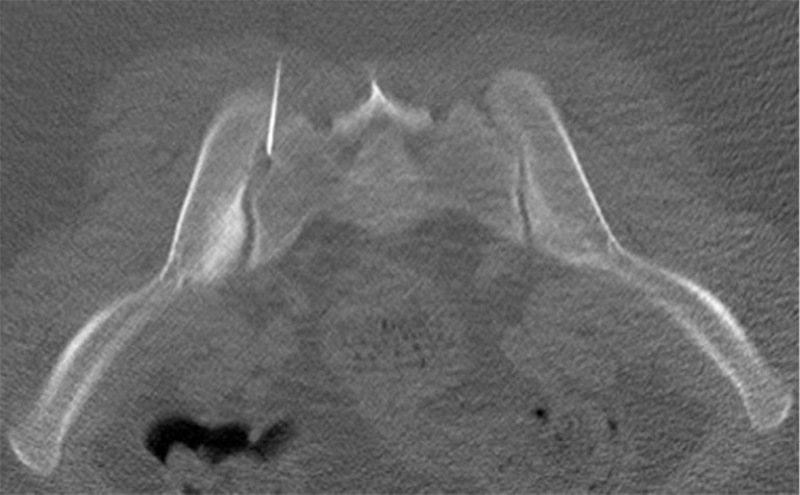

Hình ảnh chụp MRI viêm khớp cùng chậu

Hình ảnh Mri viêm khớp cùng chậu

Viêm khớp cùng chậu gây ra tình trạng dính khớp hoặc bắc cầu xương

Viêm khớp cùng chậu xuất hiện biến chứng

Viêm khớp cùng chậu đã biến chứng thành phù tủy xương, xói mòn hoàn toàn khớp cùng chậu